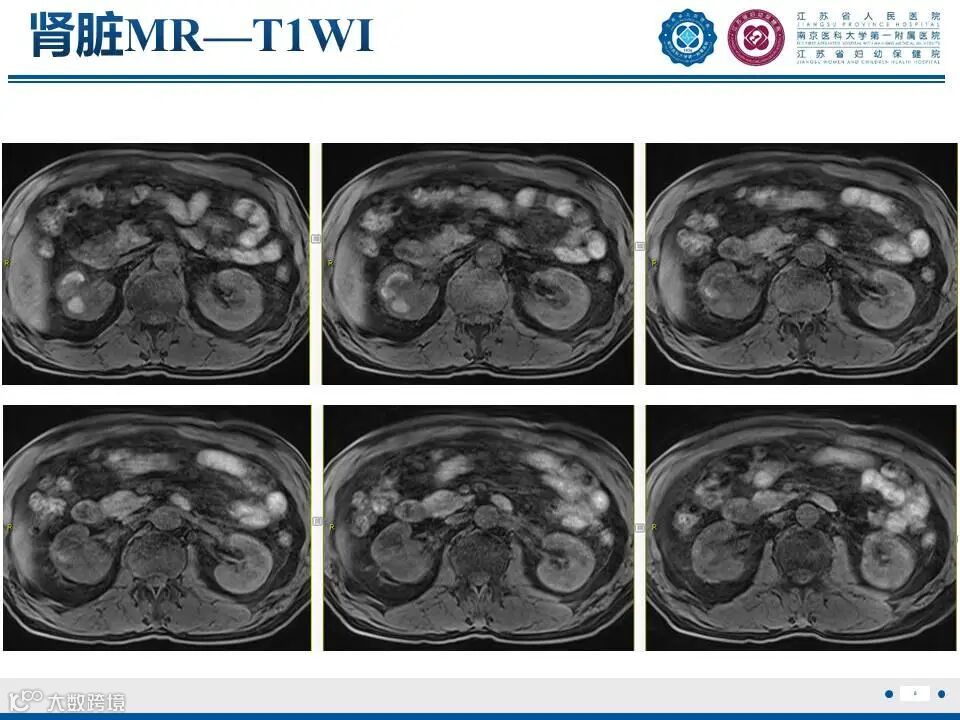

肾实质肾盂尿路上皮癌——水泄不通 II

肾实质肾盂尿路上皮癌——水泄不通 II 鼎湖影像